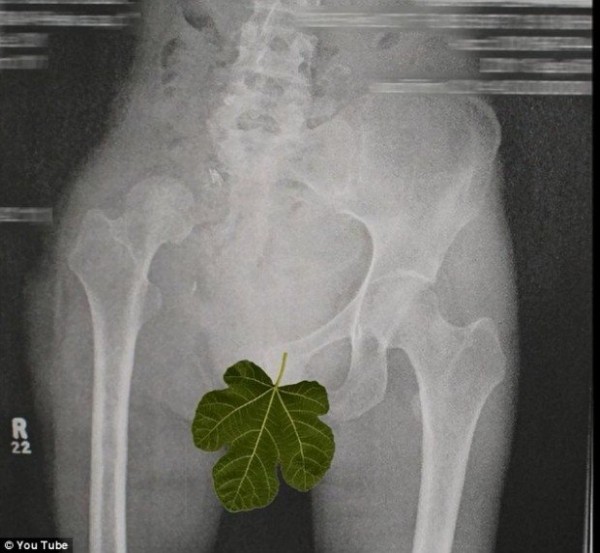

Джен О’Ши может вращать правой ногой на 180 градусов без боли и усилий, при этом ее стопа обращается к потолку. Удивительная и причудливая гибкость Джен является результатом операции, которая была проведена для того, чтобы избавить девушку от редкой формы рака кости.

После того как Джен был поставлен диагноз «Саркома Юинга», она перенесла операцию на правой ноге в 2011-м году. В ходе этой процедуры хирурги удалили всю правую половину ее таза, при этом не заменяя его протезом. Храбрая пациентка после долгих месяцев физиотерапии, благодаря которым она снова научилась ходить, к огромному своему удивлением обнаружила, что может вращать ногой на 180 градусов. Поначалу Джен стеснялась рассказывать об этом даже друзьям. Однако сейчас она поведала о своей способности всем, выложив ролик на YouTube.